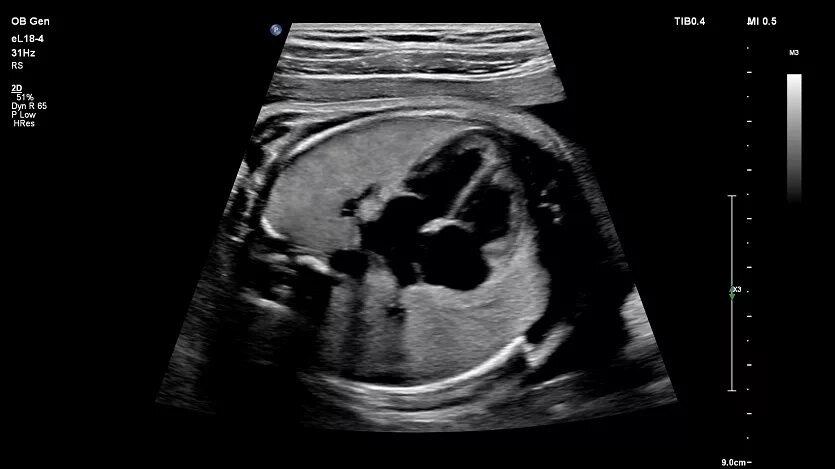

Скрининг впс